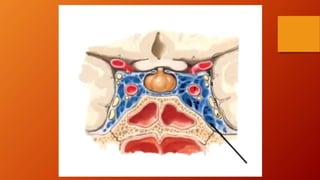

SENOS CAVERNOSOS

• Grandes plexos venosos.

• Se sitúan a cada lado de la silla turca en la

cara superior del cuerpo del esfenoides, que

contiene el seno (aéreo) esfenoidal.

• Se compone de un plexo venoso de venas con

paredes extremadamente delgadas, que se

extienden desde la fisura orbitaria superior,

anteriormente, hasta el vértice de la porción

petrosa del hueso temporal posteriormente.

• Los conductos intervenosos, anterior,

posteriormente al tallo hipofisiario.

• Dentro del seno cavernoso se hallan la arteria

carótida interna , con sus pequeñas ramas,

rodeada por el plexo carotideo nervioso

simpatico el nervio abducens (NC VI), los

nervios locomotor (NC III) y troclear (NC IV),

así como dos de las tres divisiones del nervio

trigémino (NC V), se hallan englobados en la

pared lateral del seno.